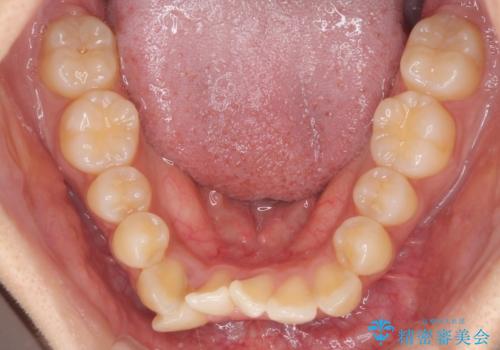

- 前歯のデコボコやクロスバイトと上顎の前突感による口の閉じにくさを気にして来院された患者様です。

目立たない装置を希望されたので、上顎が裏側装置のハーフリンガルを選択し、上下左右の小臼歯(計4歯)を抜歯して矯正治療を行うこととしました。